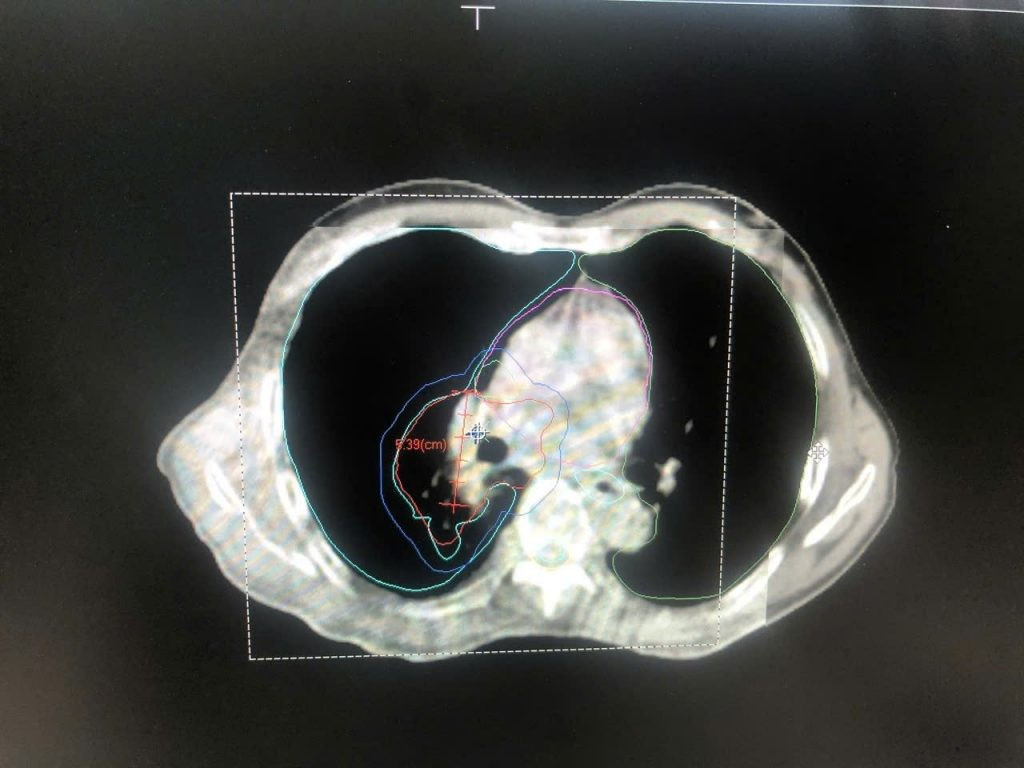

Hình ảnh CT mô phỏng cho bệnh nhân ung thư phổi để lập kế hoạch điều trị. Ảnh BV

Hình ảnh cận lâm sàng cho thấy khối ung teo nhỏ sau 5 buổi điều trị. Ảnh BV

Sau một chu kỳ hóa trị và 18 lần xạ trị, khối u của bệnh nhân đã teo nhỏ đáng kể, giảm kích thước đến 60% so với ban đầu. Bên cạnh đó, người bệnh không còn ho ra máu, hết đau ngực, hết ho dai dẳng.